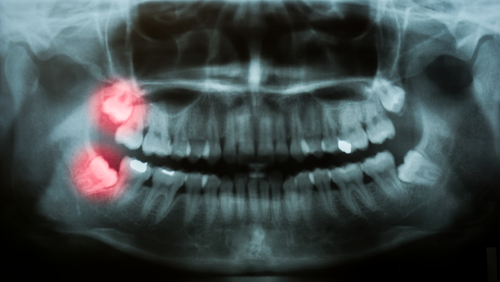

wisdom teeth on x-ray

The top reason why most wisdom teeth need to be removed is that there’s simply not enough room in the mouth for these new teeth. Your dental x-rays will show your dentist whether or not there will be enough space for your wisdom teeth. However, if your mouth doesn’t have adequate room and you do not have your wisdom teeth removed, it can lead to overcrowding, crooked teeth, or even an impaction. Having impacted wisdom teeth essentially means that the teeth are stuck in your bone below the gum line. This can be very painful and increases the risk of infection.

Wisdom teeth also have a funny way of working themselves sideways and start to come through horizontally rather than vertically through the gums. If this occurs, nearby healthy teeth can be seriously damaged and your bite can be affected, causing larger, more serious, and painful problems.